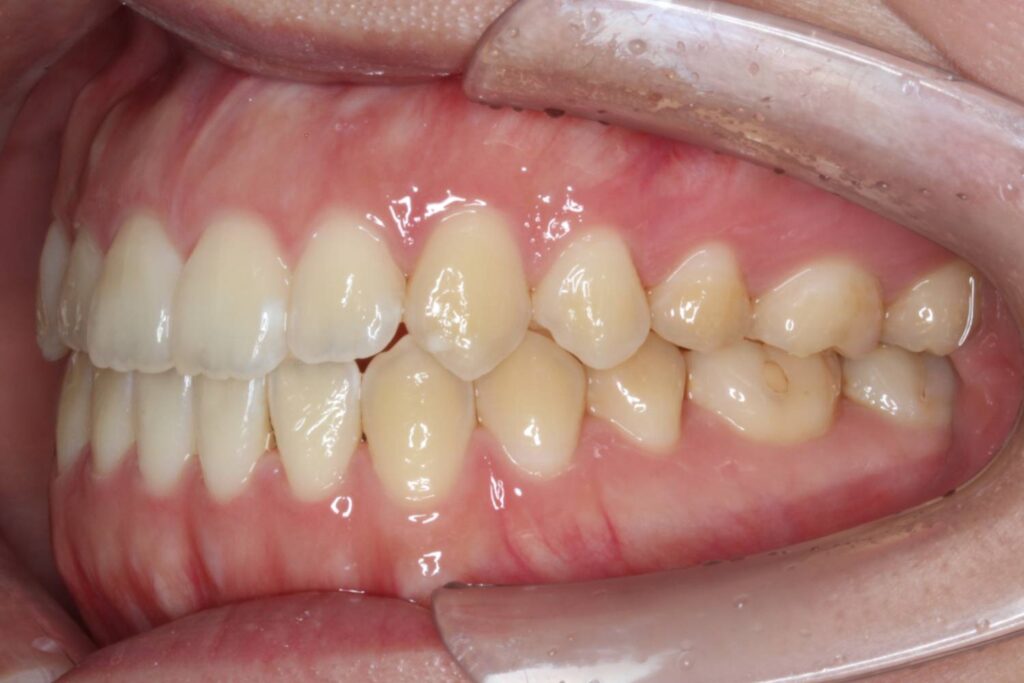

After

インビザラインは臼歯を「圧下」させることによって前歯を伸び出させずに開咬を治せるため、開咬に適した装置と言えます。

治療後は前歯もしっかりと噛み合うことで、機能的な歯並びを獲得することができました。